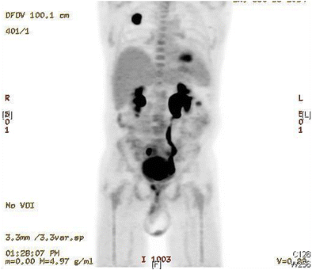

Fig. 2